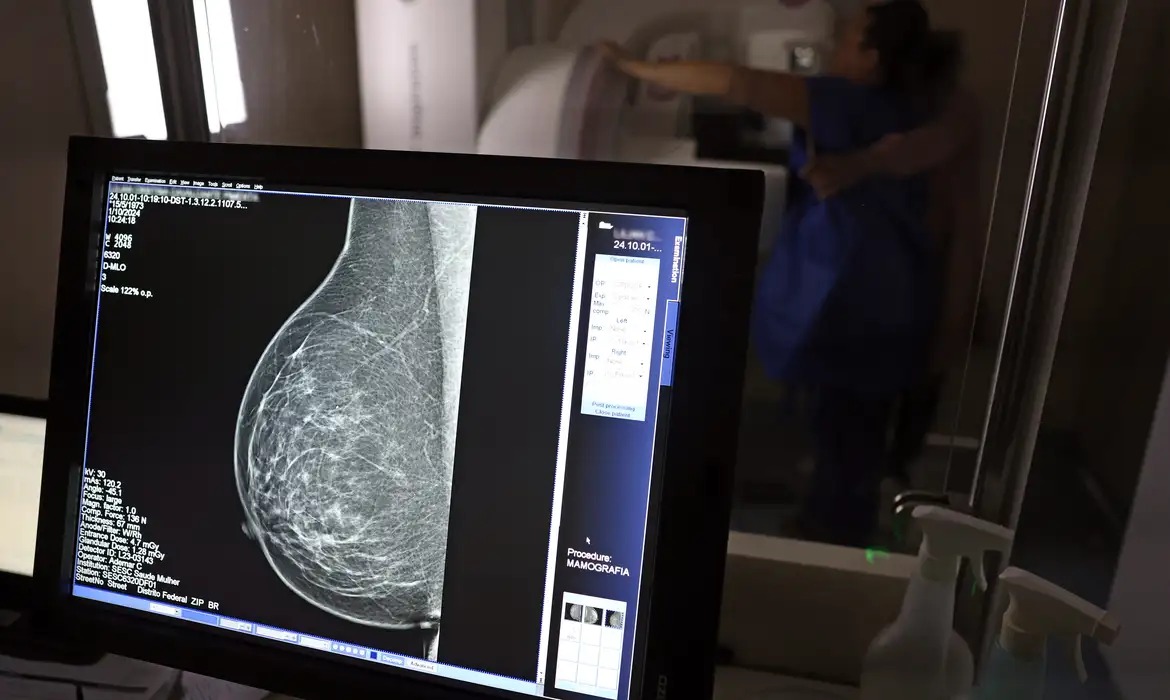

O Ministério da Saúde passou a recomendar o acesso a mamografia, via Sistema Único de Saúde (SUS), para mulheres de 40 a 49 anos – mesmo que não haja sinais ou sintomas de câncer de mama. De acordo com a pasta, a faixa etária concentra 23% dos casos da doença, e a detecção precoce aumenta as chances de cura.

Até então, a orientação era que o exame fosse feito a partir dos 50 anos.

A medida faz parte de um conjunto de ações anunciadas nesta terça-feira (23) voltado para a melhoria do diagnóstico e da assistência. A recomendação para mulheres a partir dos 40 anos é que o exame seja feito sob demanda, em decisão conjunta com o profissional de saúde.

“A paciente deve ser orientada sobre os benefícios e desvantagens de fazer o rastreamento. Mulheres nesta idade tinham dificuldade com o exame na rede pública de saúde por conta da avaliação de histórico familiar ou necessidade de já apresentar sintomas”, informou o ministério em nota.

As mamografias via SUS em pacientes com menos de 50 anos, de acordo com a pasta, representam 30% do total, o equivalente a mais de 1 milhão apenas no ano de 2024.

Outra medida anunciada é a ampliação da faixa etária para o rastreamento ativo – quando a mamografia é solicitada de forma preventiva a cada dois anos. A idade limite, até então, era 69 anos. Agora, passa a ser 74 anos. Dados do ministério revelam que quase 60% dos casos de câncer de mama estão concentrados entre 50 e 74 anos.

“A ampliação do acesso à mamografia aproxima o Brasil de práticas internacionais, como as adotadas na Austrália, e reforça o compromisso em garantir diagnóstico precoce e cuidado integral às mulheres brasileiras. O câncer de mama é o mais comum e o que mais mata mulheres, com 37 mil casos por ano”, reforçou a pasta.

Os números mostram que, em 2024, cerca de 4 milhões de mamografias para rastreamento e 376,7 mil exames diagnósticos foram realizados no SUS.